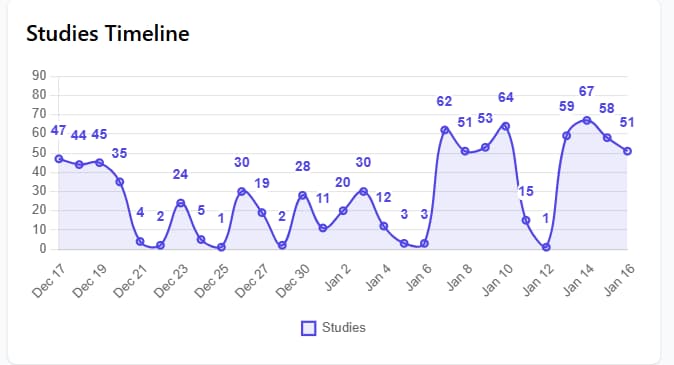

Sobre Nosotros

Nuestra Trayectoria en PACS en la Nube

Desde nuestros inicios en 2014, Dicomline nació con la visión de transformar la imagenología médica a través de la tecnología en la nube. Detectamos una necesidad urgente: que médicos y especialistas pudieran acceder a imágenes e informes médicos de manera ágil, segura y desde cualquier lugar.

Fuimos pioneros en desarrollar un Sistema de Comunicación y Archivo de Imágenes (PACS) robusto, seguro y escalable, completamente basado en la nube. Nuestro propósito es empoderar a los profesionales de la salud con herramientas modernas, intuitivas y siempre disponibles.

A lo largo de los años, hemos mantenido un compromiso inquebrantable con la innovación y la mejora continua, consolidándonos como un socio estratégico para clínicas, hospitales y centros de diagnóstico.

¿Listo para transformar su práctica?

Únase a miles de profesionales de la salud que ya utilizan DicomLine.